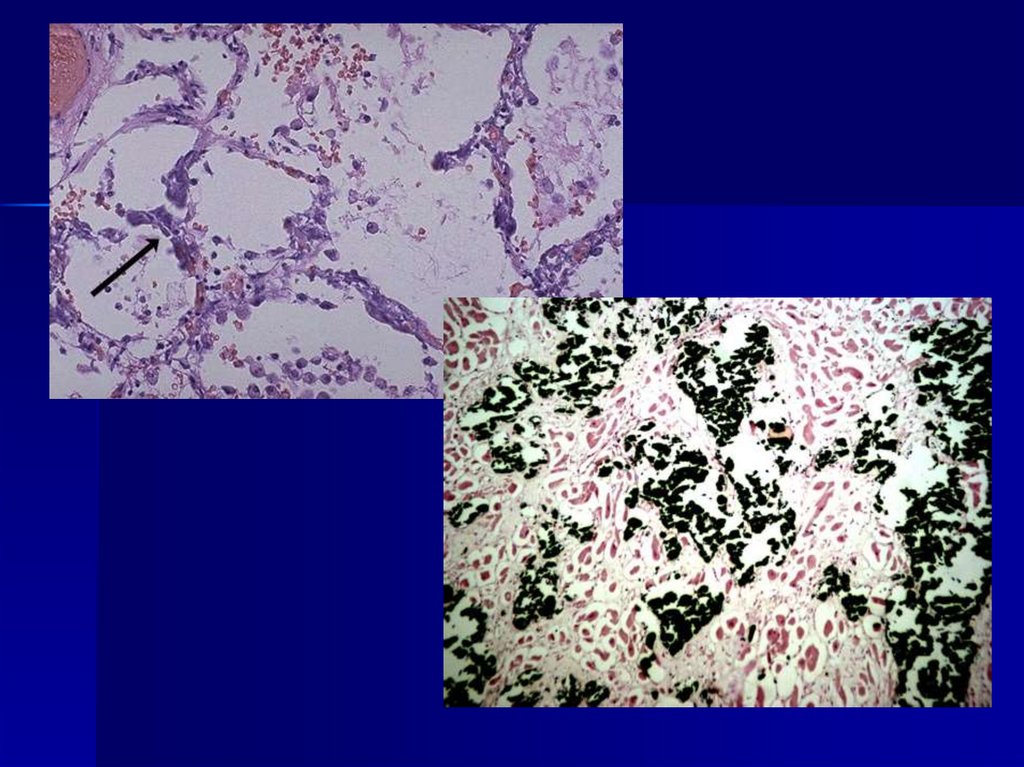

6. Бурая индурация легкого.

1 – макрофаги с гемосидерином в альвеолах, 2 – утолщение межальвеолярных перегородок.